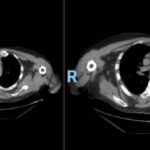

En la tomografía computada de tórax en ventana mediastínica se observan múltiples adenopatías localizadas en diversas áreas del cuello y mediastino. Estas adenopatías se distribuyen en las cadenas yúgulo-carotídeas, en ambas regiones supraclaviculares y a lo largo del mediastino, abarcando específicamente las siguientes áreas: la región paratraqueal superior derecha, los espacios retrocavo-pretraqueal y prevascular, la zona subcarinal, la ventana aortopulmonar y en la región de la arteria mamaria (AM). La presencia de estas adenopatías sugiere un compromiso linfático difuso en estas zonas.